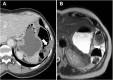

Management of peritoneal surface malignancies is currently entrusted to a multimodality approach. Computed tomography (CT) scan remains the first imaging method despite the limitations in identifying small implants in critical regions. Magnetic resonance imaging is usually recommended for its performance in small implants, mesentery, and small bowel assessment. Positron emission tomography/CT plays an important role only in pseudomyxoma peritonei. Thus, becoming aware of the imaging strengths and drawbacks and having a multimodality imaging approach might be the best option for the patients.